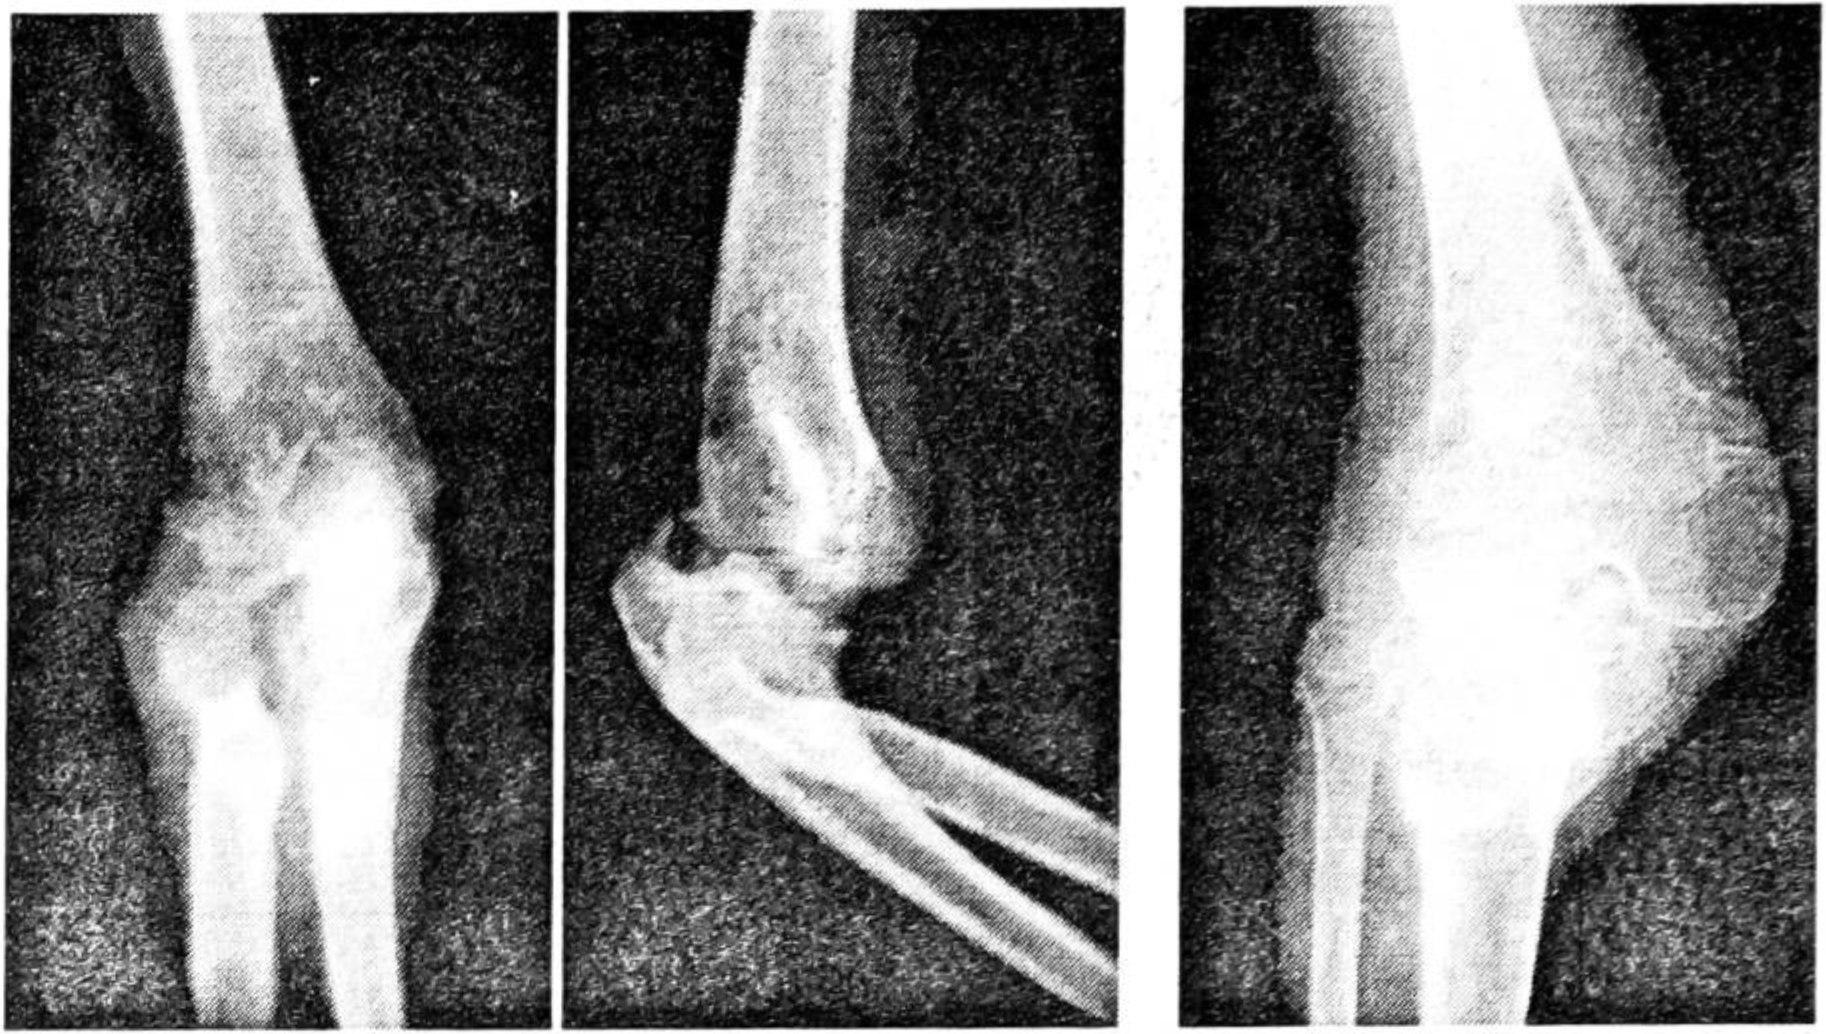

При ожоговом истощении возникают нарушения репаративных процессов в ране, генерализованный остеопороз, атрофические явления в мышцах и связках, подвывихи и вывихи в крупных суставах (рис. 2), снижается масса тела, что затрудняет дальнейшее лечение.

Рис. 2. Развитие у больной с ожоговым истощением остеопороза, подвывихов в локтевом и коленном суставах.